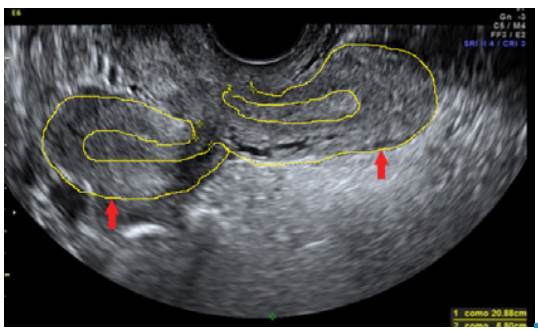

Considering the symptoms, pregnancy or infection of the urogenital tract were suspected; paraclinical results showed negative pregnancy test, blood count with leukocytosis without neutrophilia (leukocytes 15 300 and neutrophils 61.6%), without anemia (hemoglobin 14.2 gr/L, hematocrit 41%) and platelets 433 000/uL. Urinalysis did not suggest urinary tract infection. Transvaginal ultrasound and abdominal pelvic tomography were requested, revealing uterus didelphys (Figure 1) and renal agenesis (Figure 2).

Transvaginal gynecology ultrasound showing the presence of uterus didelphys (demarcated in yellow).

Figure 1: Transvaginal gynecology ultrasound showing the presence of uterus didelphys (demarcated in yellow).

Source: Document obtained during the study.